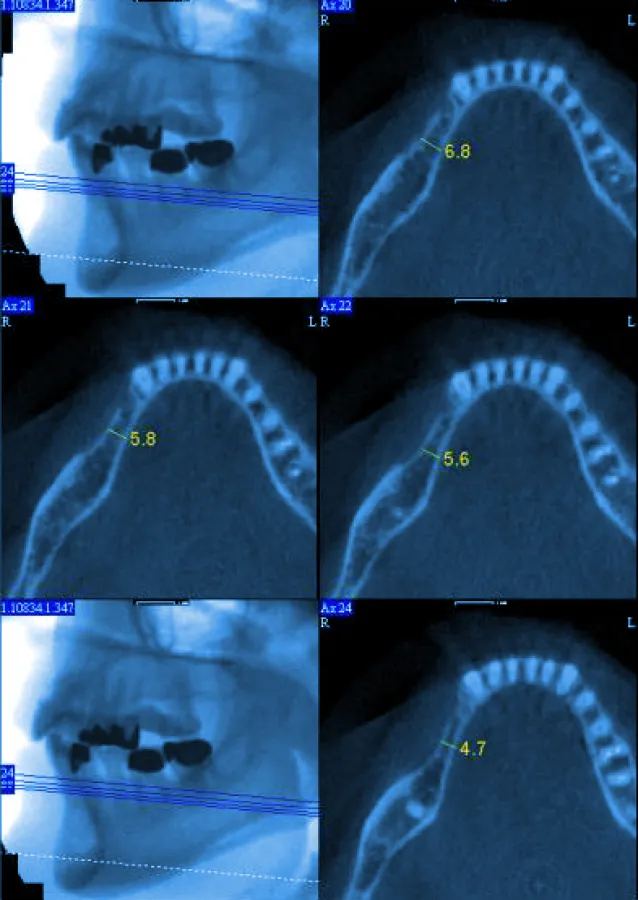

Wie die Computertomographie ermöglicht die digitale Volumentomographie durch metrisch genaue anatomische Abbildungen des Kiefers exakte Planungsmöglichkeit der Implantate, jedoch bei geringerer Strahlenbelastung für den Patienten. Für ein exaktes 3D-Bild des Kiefers rotieren Sender-Detektoren etwa eine Minute um den Kopf des Patienten und führen insgesamt 360 Einzelprojektionen durch. Mit Hilfe dieser Kieferrekonstruktion erstellt der Chirurg auf seinem Computer ein virtuelles Implantat und passt es exakt dem Knochenbau des Patienten an. Bereits im Vorfeld entstehen so die genauen Passdaten für Form, Ausrichtung und Position der Implantate, die dann als Grundlage für die eigentliche Operation dienen.

Im Zentrum für Zahnimplantologie der Estetica Clinic in Hamburg kommt der digitale Volumentomograph "New Tom" bereits seit zwei Jahren erfolgreich zum Einsatz und bildet das Herzstück des Zentrums für Implantatdiagnostik (ZID). Dr. Carsten Knebel, Facharzt für Mund-, Kiefer- und Gesichtschirurgie und einer der beiden Leiter der Estetica Clinic: "Volumentomographie ist aus der modernen Implantatplanung nicht mehr weg zu denken. Durch eine zehntelmillimeter-genaue 3D-Abbildung des Kiefers können wir jedes Implantat individuell auf die Anatomie des Patienten abstimmen und ausrichten. Anhand der digitalen Bilddatensätze bestimmen wir mögliche Komplikationen bereits im Voraus und vermeiden somit Schädigungen an Kiefer oder Nerven. Volumentomographie bietet ein Maximum an Sicherheit für den Patienten."